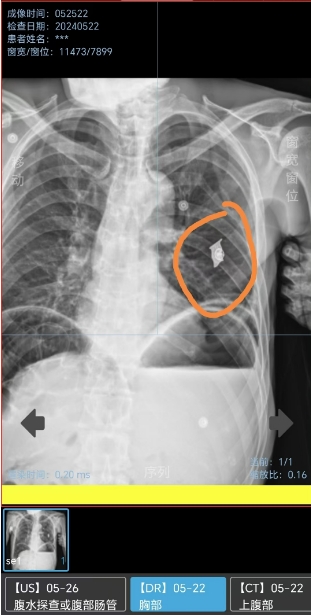

“手术当天CT检查时,显示赵爷爷的左侧肺部被切除了三分之二,胸腔里面还留有一个弹片。”戴主任表示,得知赵爷爷故事后,大家对老人越发敬重。“那天还是我抱他上的手术台,我还感叹这个老人怎么只有80多斤。”戴少华感慨道。

患者术后影像。